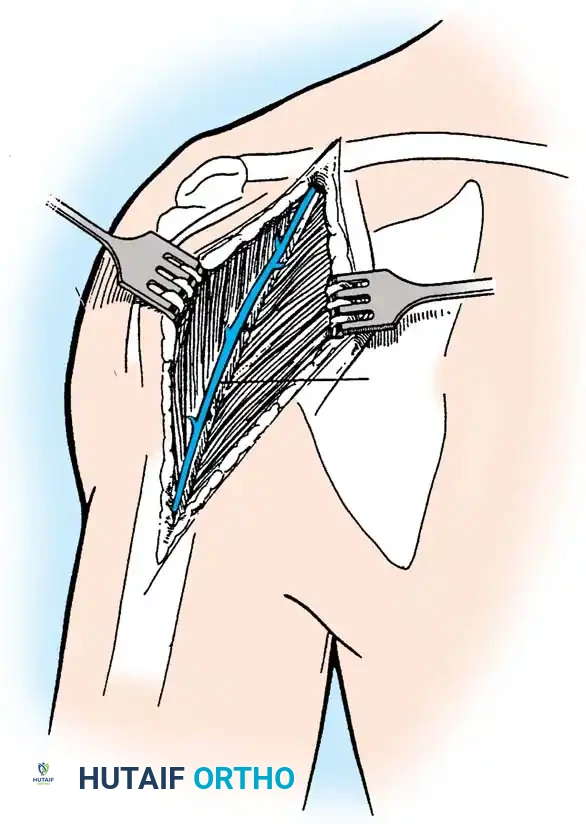

2. Subscapularis Management

The subscapularis is the gatekeeper to the joint. It can be managed via a tenotomy (1 cm medial to the lesser tuberosity), a lesser tuberosity osteotomy (LTO), or a subscapularis peel. LTO provides superior bone-to-bone healing and is increasingly favored.

Securely repair the subscapularis using heavy non-absorbable sutures through transosseous tunnels.